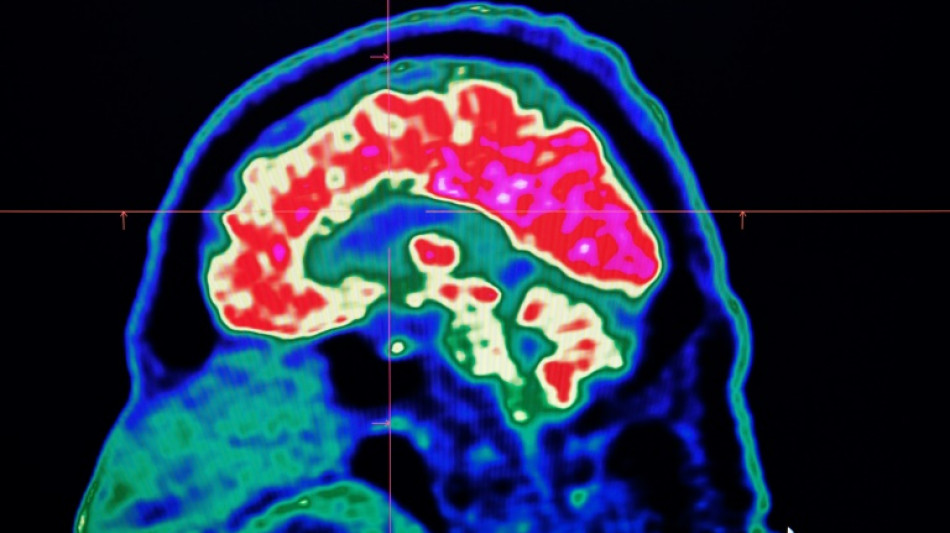

What are all these microplastics doing to our brains?

What are all these microplastics doing to our brains? / Photo: Fred TANNEAU - AFP/File

Tiny shards of plastic called microplastics have been detected accumulating in human brains, but there is not yet enough evidence to say whether this is doing us harm, experts have said.

These mostly invisible pieces of plastic have been found everywhere from the top of mountains to the bottom of oceans, in the air we breathe and the food we eat. They have also been discovered riddled throughout human bodies, inside lungs, hearts, placentas and even crossing the blood-brain barrier.

The most prominent study looking at microplastics in brains was published in the journal Nature Medicine in February.

The scientists tested brain tissue from 28 people who died in 2016 and 24 who died last year in the US state of New Mexico, finding that the amount of microplastics in the samples increased over time.

The study made headlines around the world when the lead researcher, US toxicologist Matthew Campen, told the media that they detected the equivalent of a plastic spoon's worth of microplastics in the brains.

Campen also told Nature that he estimated the researchers could isolate around 10 grammes of plastic from a donated human brain -- comparing that amount to an unused crayon.